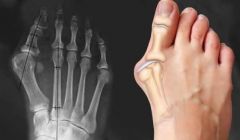

Новый онлайн-курс по массажу при проблемах связанных с искривлением большого пальца стопы, образованием 'шишки', 'косточки' на ноге, плоскостопии и сопутствующих патологиях

Положительный и достаточно быстрый эффект от процедуры, достигается благодаря грамотному последовательному подходу, который основан на биомеханических взаимосвязях, рефлекторных реакциях и коррекции скелета стопы. При проведении такого массажа, в организме массируемого происходит множество положительных биохимических процессов и ответных реакций как на клеточном, так и на тканевом уровнях. В частности, улучшается микроциркуляция и питание тканей стопы и голени, улучшается проводимость сосудов, как следствие устраняются застойные явления и отечность ног, восстанавливается эластичность связок и сухожилий. В совокупности это положительно влияет на здоровье ног. Уходит болезненность в области переднего отдела стопы, в частности в зоне вальгусного искривления и образования типичного выступа, известного как «шишка» или «косточка» на большом пальце стопы. Шаг становится более мягким, лёгким, непринуждённым, естественным.

Урок №4. Система большого пальца стопы. Вальгусная деформация, механизм развития патологии, биомеханика

Урок №5. Методика и техника массажа при вальгусной деформации большого пальца стопы. Протокол работы